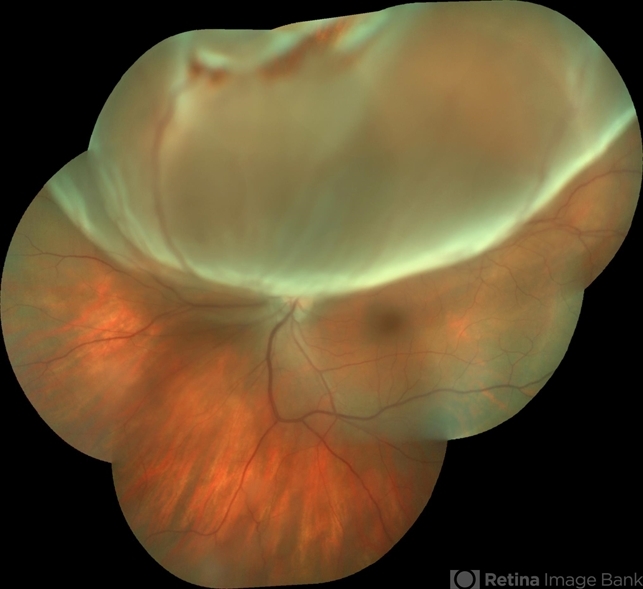

- detachment, bullous retinal detachment, rupture

Camera Background Topcon TRC-50 Dx - IA, keystone field photographic 35 Degrees. Composition automatic Imaginet with manual adjustment. - Description

- Patient female, 28-years-old, low subtle vision after exercises weight. Holder of 8 degrees of myopia and already with a history of degeneration myopia peripheral in both eyes.